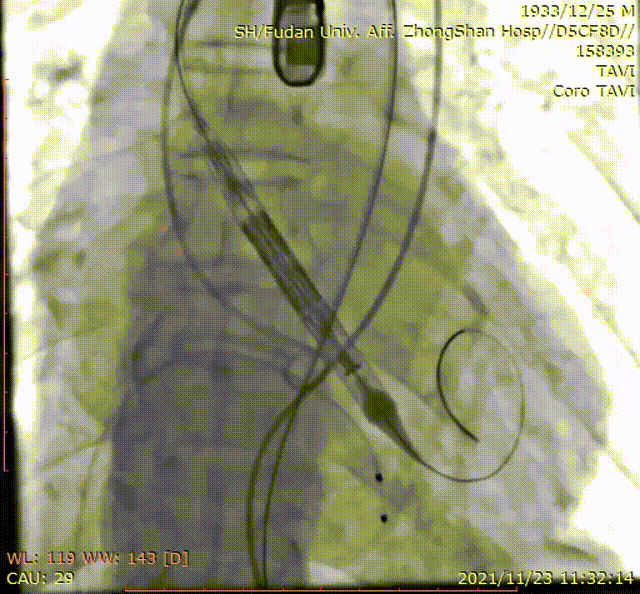

手术过程

输送系统到位

定位环释放

瓣膜精准定位

本例临床试验的患者是一例单纯性重度主动脉瓣关闭不全患者。在手术过程中,这款瓣膜产品使用体验非常流畅,仅仅31分钟就完成了手术。